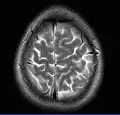

Brain regions on T1 MRI -

Normal axial T2-weighted MR image of the brain -